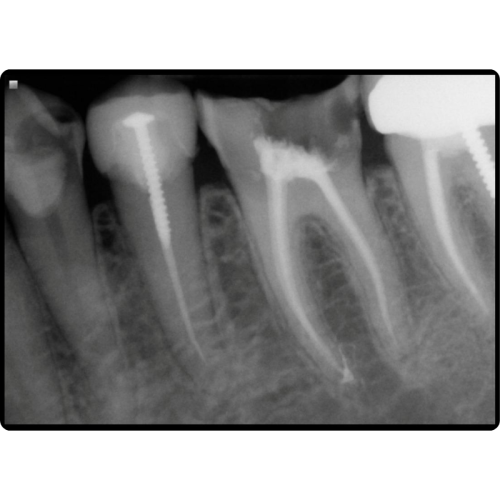

Root Canal Therapy (Endodontics)

When infection or inflammation reaches the inner nerve of a tooth, root canal therapy can save it. Our advanced endodontic treatments:

- Relieve pain

- Eliminate infection

- Preserve your natural tooth

- Prevent the need for extraction

We prioritize comfort and precision, using modern techniques to ensure efficient and effective care.